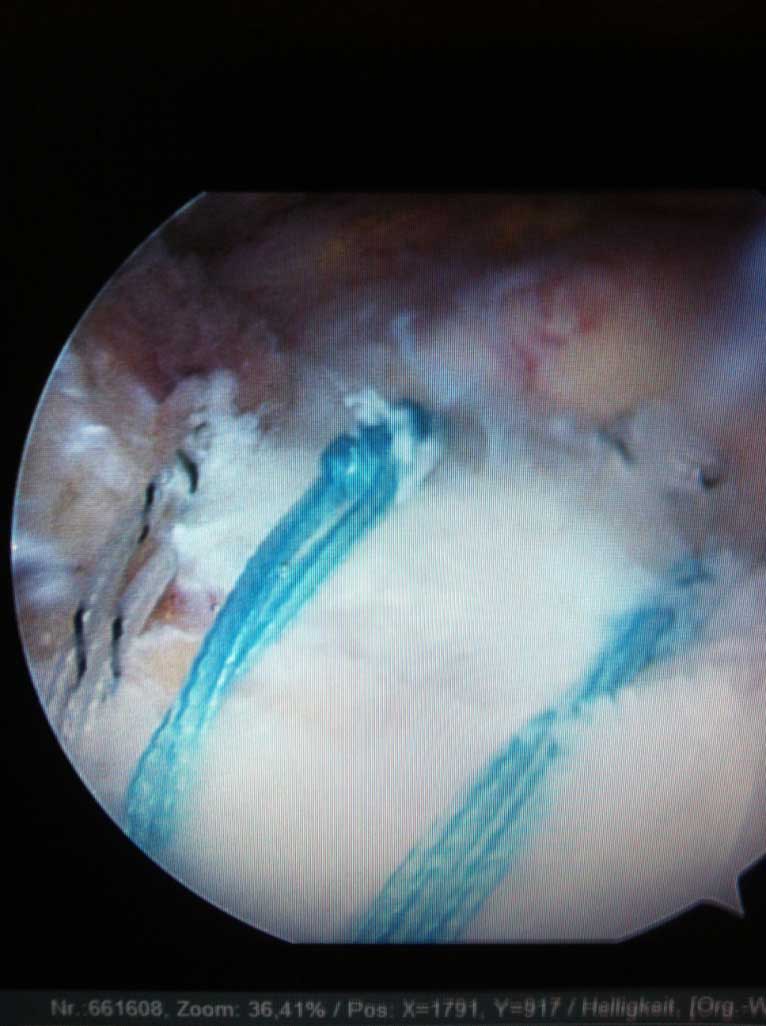

Je nach Alter, Verletzungsmuster, Anzahl der Luxationsereingnisse und weiteren Faktoren, wird eine schulterstabilisierende Operation indiziert und empfohlen. Diese führen wir ebenfalls ausschliesslich arthroskopisch

(Schüsselloch Operation) durch. Innerhalb von 15 - 30 min wird dabei der knorpelige Ring (s.g. Labrum) auf den knöchernen Pfannenrand mit speziellen Anker und Fäden wieder zurück befestigt.

Die operationsbedürftigen Verletzungen versorgen wir mit kleinen Implantaten arthroskopisch. Im Gegensatz zu Versorgung mit Platten oder Drähte ist bei unserem arthroskopischen Verfahren eine spätere Metallentfernung (2. Eingriff) nicht notwendig.